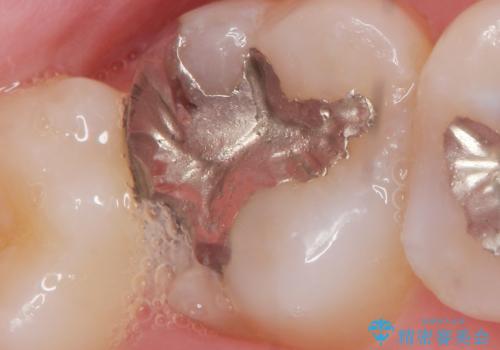

- 銀歯と親知らずの間に毎回食べ物が挟まることを自覚していたが、放置した結果虫歯が再発し検診で発覚し治療を行うこととなりました。

ゴールド治療について

上顎大臼歯など目に触れにくく大きな力のかかる部位は、ゴールドによる修復をお勧めすることがあります。